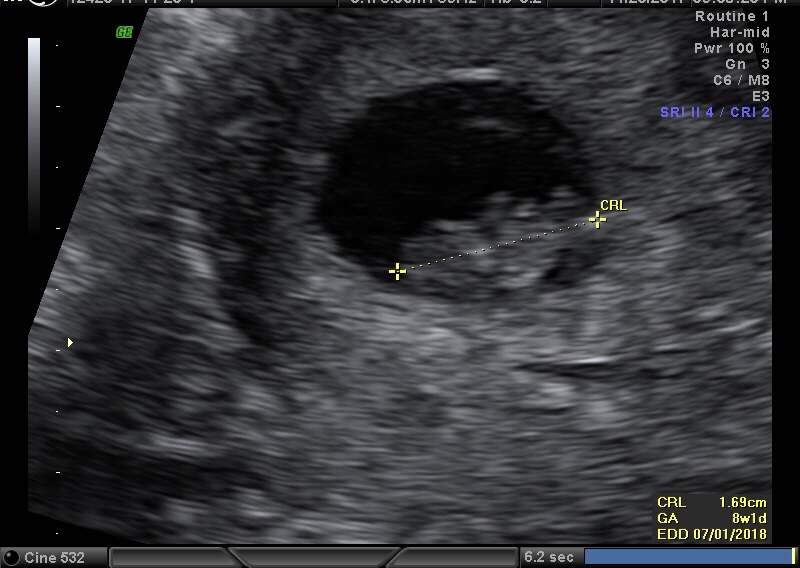

BFP #2 10/14/17, EDD 7/1/18

I feel like such an ass. we got family pics done yesterday by the same people that did our wedding pics 10 yrs ago and DS' newborn shots 5 years ago. I took an ultrasound pic with us to get a shot of ds holding it up. I knew they had losses before their daughter a couple years ago. But it came up they had another just this fall. I felt so bad cause here I come, with an ultrasound pic, when she's saying how rough that loss was for her.

We had a hectic day today since our NT was at 7am. Everything looked perfect, and our little bean looks like a baby. Just waiting for our NIPT to come back before announcing.